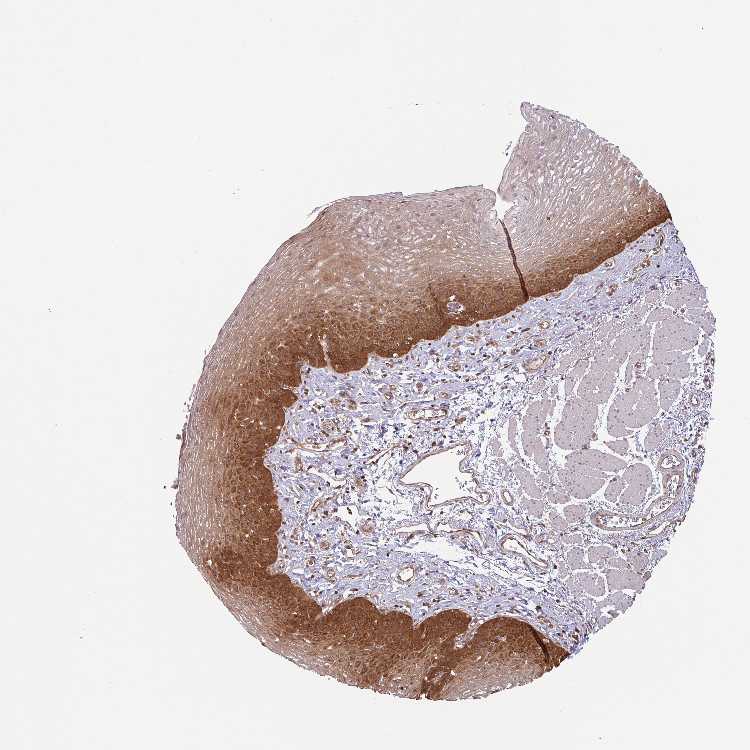

ESOPHAGUS - Antibody stainingi

Antibody staining in the annotated cell types in the current human tissue is reported as not detected, low, medium, or high, based on conventional immunohistochemistry profiling in selected tissues. This score is based on the combination of the staining intensity and fraction of stained cells.

Each image is clickable and will lead to virtual microscopy that enables deeper exploration of all samples and also displays staining intensity scores, fraction scores and subcellular localization as well as patient and tissue information for each sample.

Antibody HPA049911Antibody CAB010161

Squamous epithelial cells HighNot detected